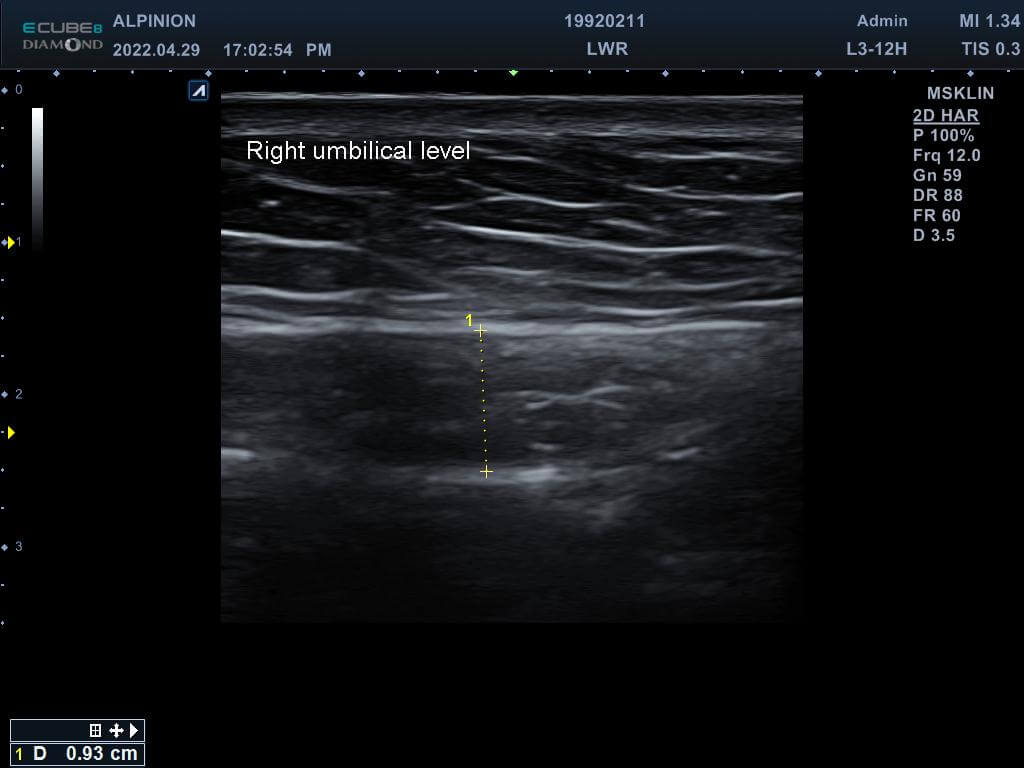

專業的醫師先在磁刺激前測量林小姐的腹直肌厚度,發現雙側的腹直肌分別為0.81cm(右側)與0.78cm(左側),同時雙側白線的距離也長達1.96cm,已經達到腹直肌分離的狀況。在使用了四周共8次的增肌減脂機後,雙側的腹直肌增厚為0.93cm(右側)與0.82cm(左側),同時雙側白線的距離減少1.46cm並明顯增厚,代表結締組織已經增生修復了。

增肌減脂(後)右側肚臍高度腹直肌增厚為0.93cm